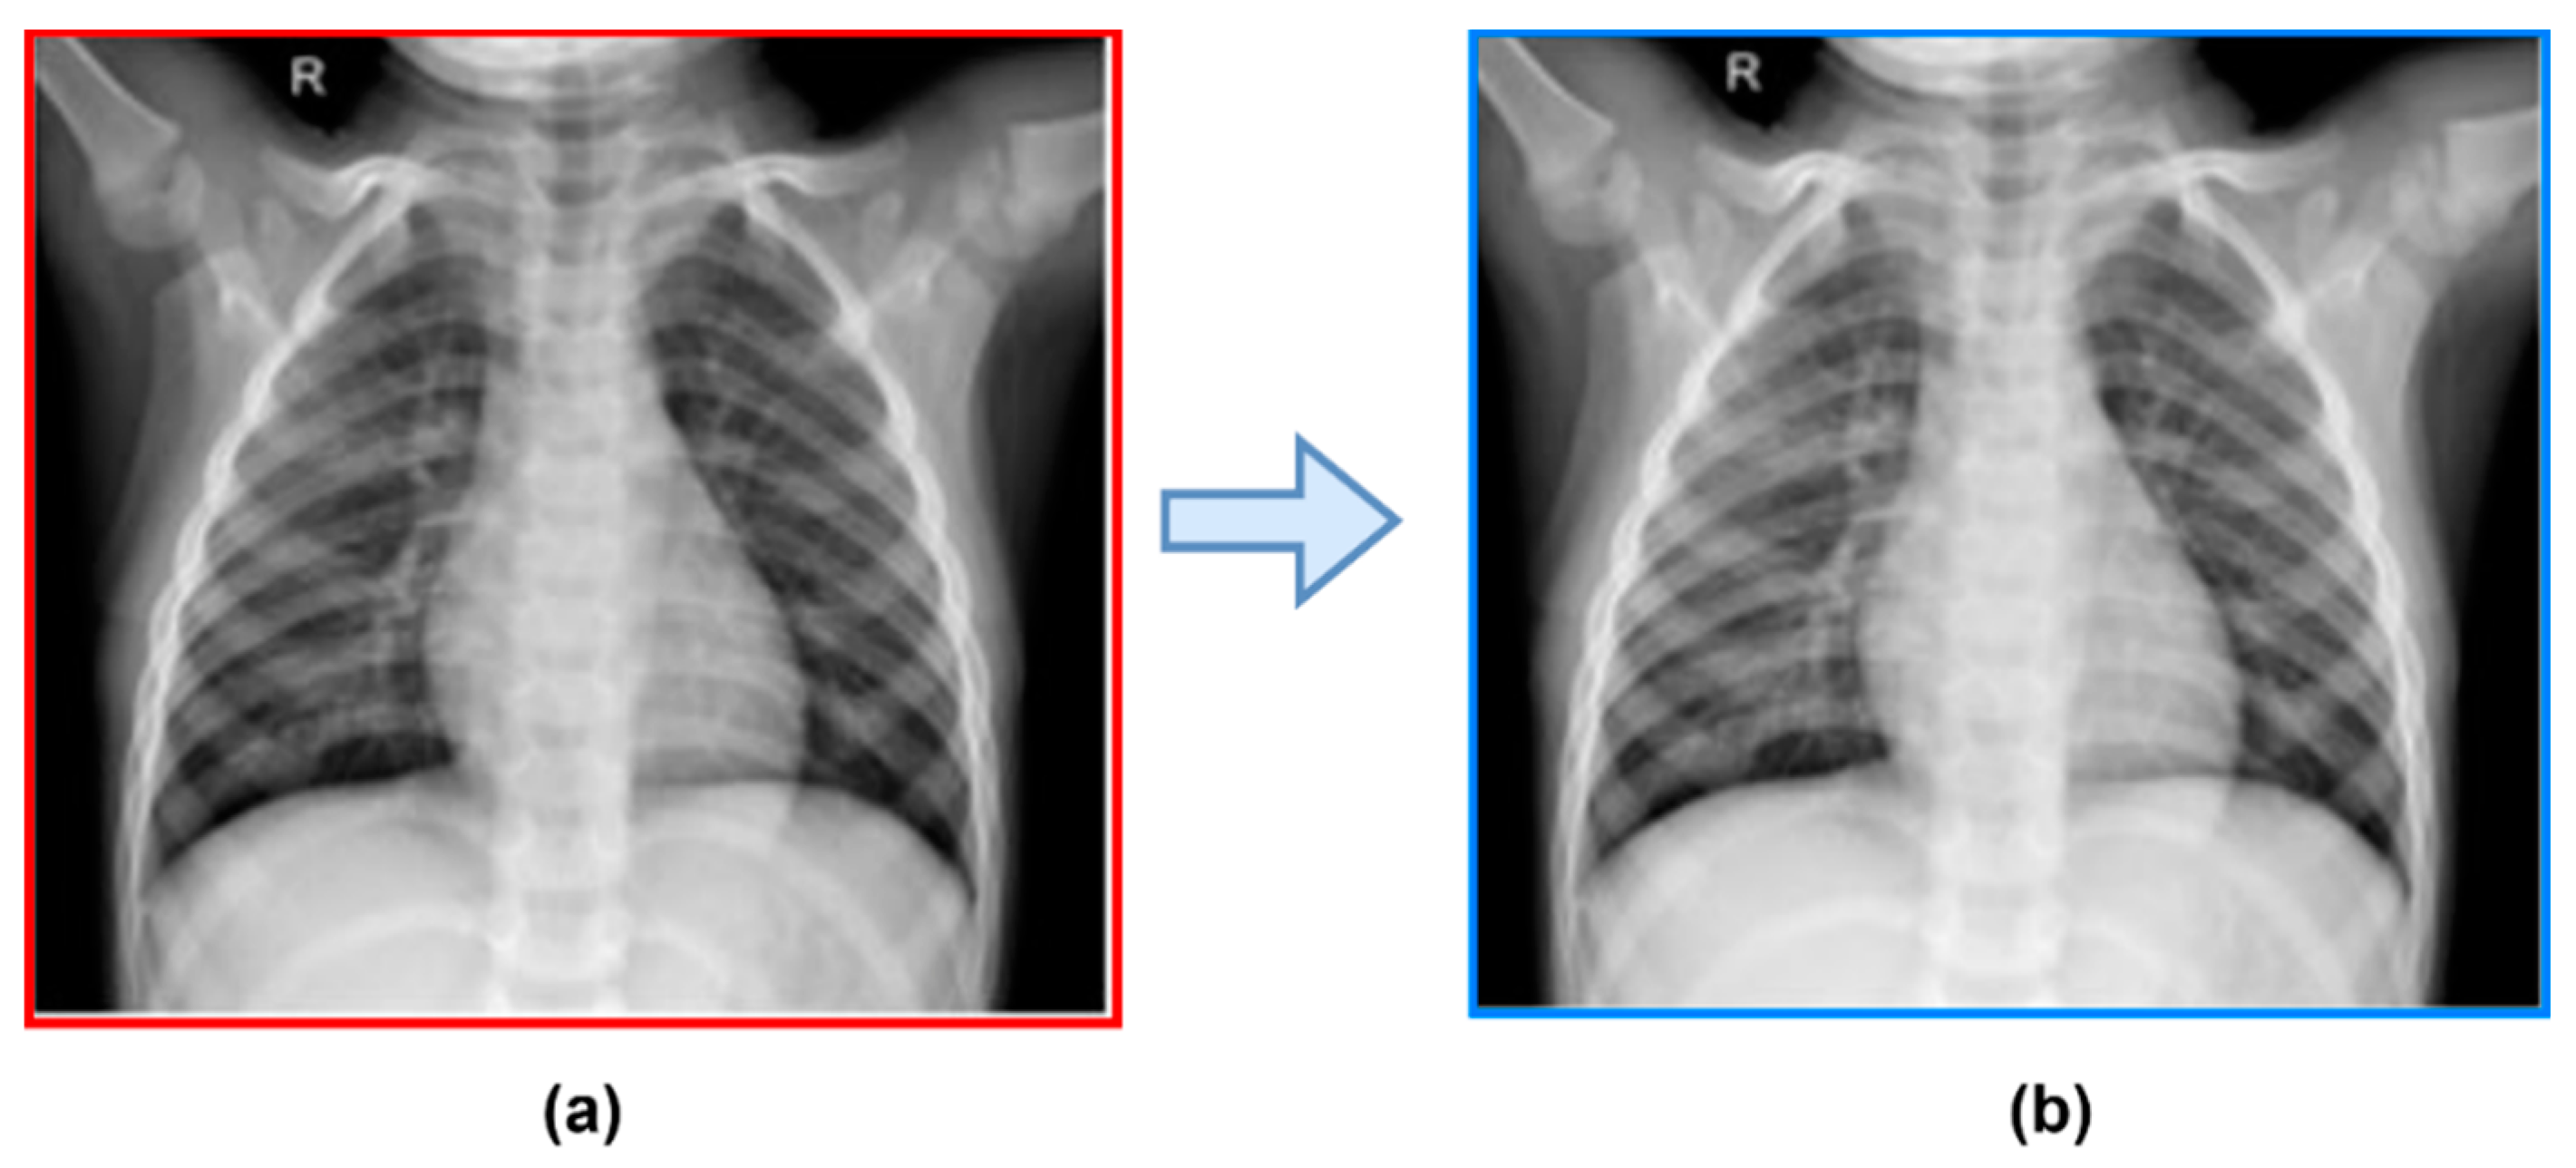

3.2.1. Pre-Processing Steps

| Step 1: | Pre-process image = X and Pre-processing step is applied by using: (a) Resize Chest X-Ray image (X) to (299, 299) [Enhanced Chest X-Ray image by preprocessing steps] (a) Remove Noise using Gaussian smoothing operator, and (b) Enhance local contrast logarithmic operator |